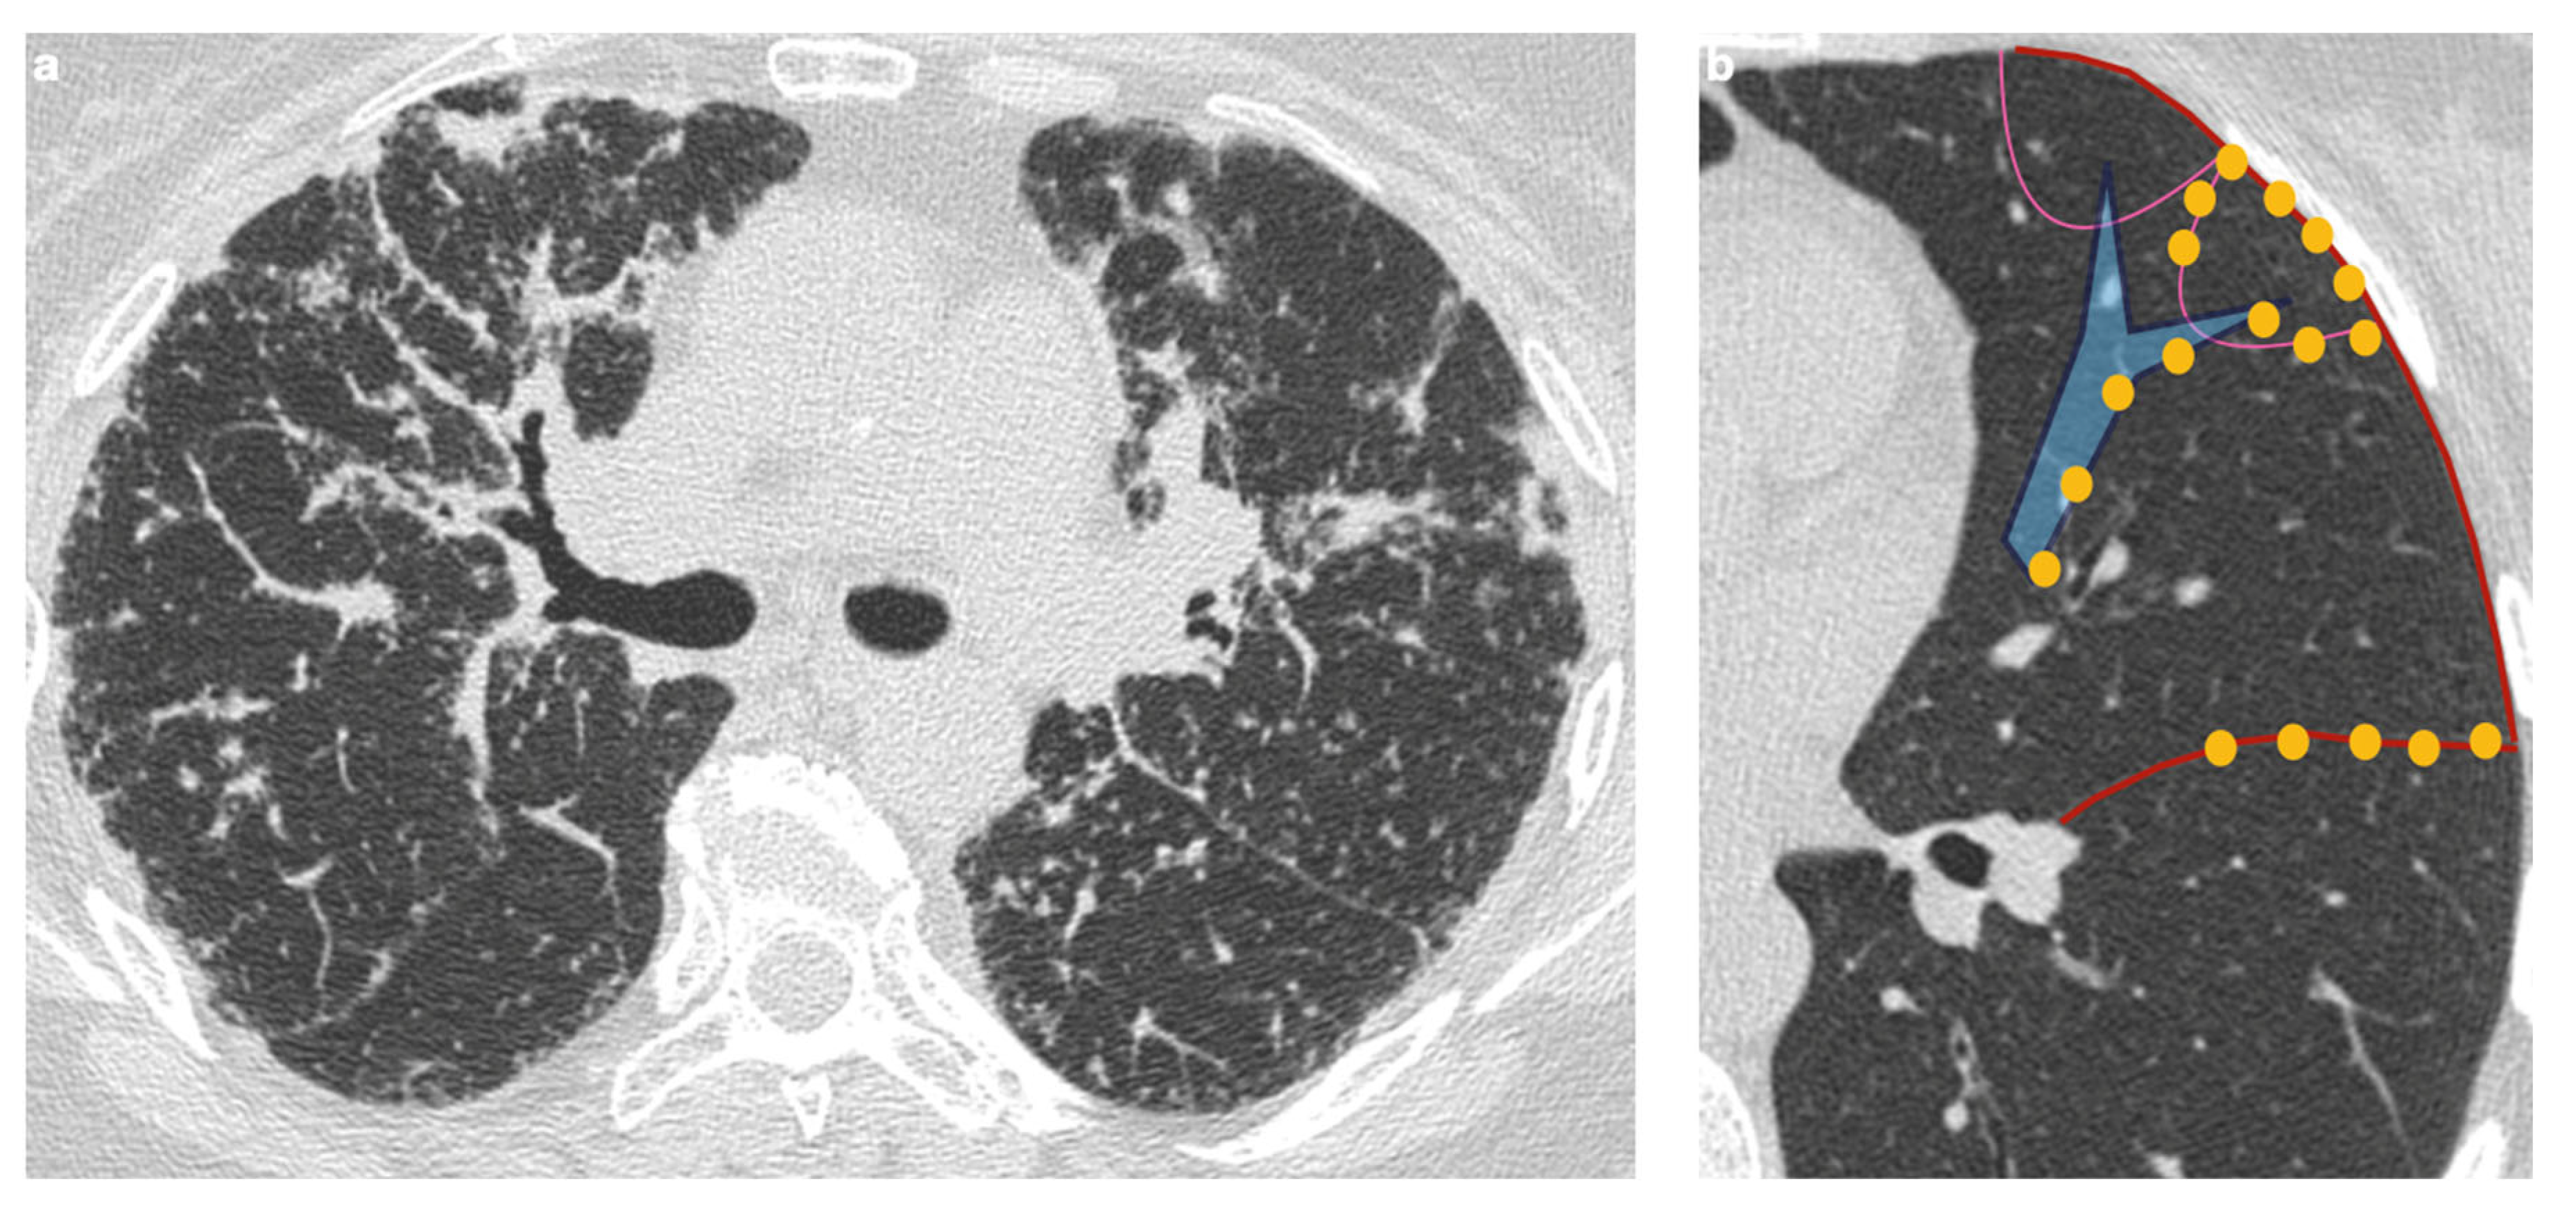

4.2.1. Nodules and Masses

- Nakatsu, M.; Hatabu, H.; Morikawa, K.; Uematsu, H.; Ohno, Y.; Nishimura, K.; Nagai, S.; Izumi, T.; Konishi, J.; Itoh, H. Large Coalescent Parenchymal Nodules in Pulmonary Sarcoidosis: “Sarcoid Galaxy” Sign. Am. J. Roentgenol. 2002, 178, 1389–1393. [Google Scholar] [CrossRef] [PubMed]

- Herráez Ortega, I.; Alonso Orcajo, N.; López González, L. El “cúmulo sarcoideo”. Un nuevo signo en tomografía computarizada de tórax de alta resolución. Radiología 2009, 51, 495–499. [Google Scholar] [CrossRef] [PubMed]